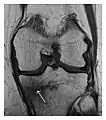

Figure 9: Proximal metaphyseal fatigue fracture of the tibia in a 27-year-old recent male military recruit. (a) Anteroposterior radiograph is within normal limits. (b) Coronal T1-weighted MR image shows a marked linear hypoattenuation along the medial tibial metaphysis (arrow) surrounded by diffuse hypointensity in keeping with posttraumatic edema.[1]